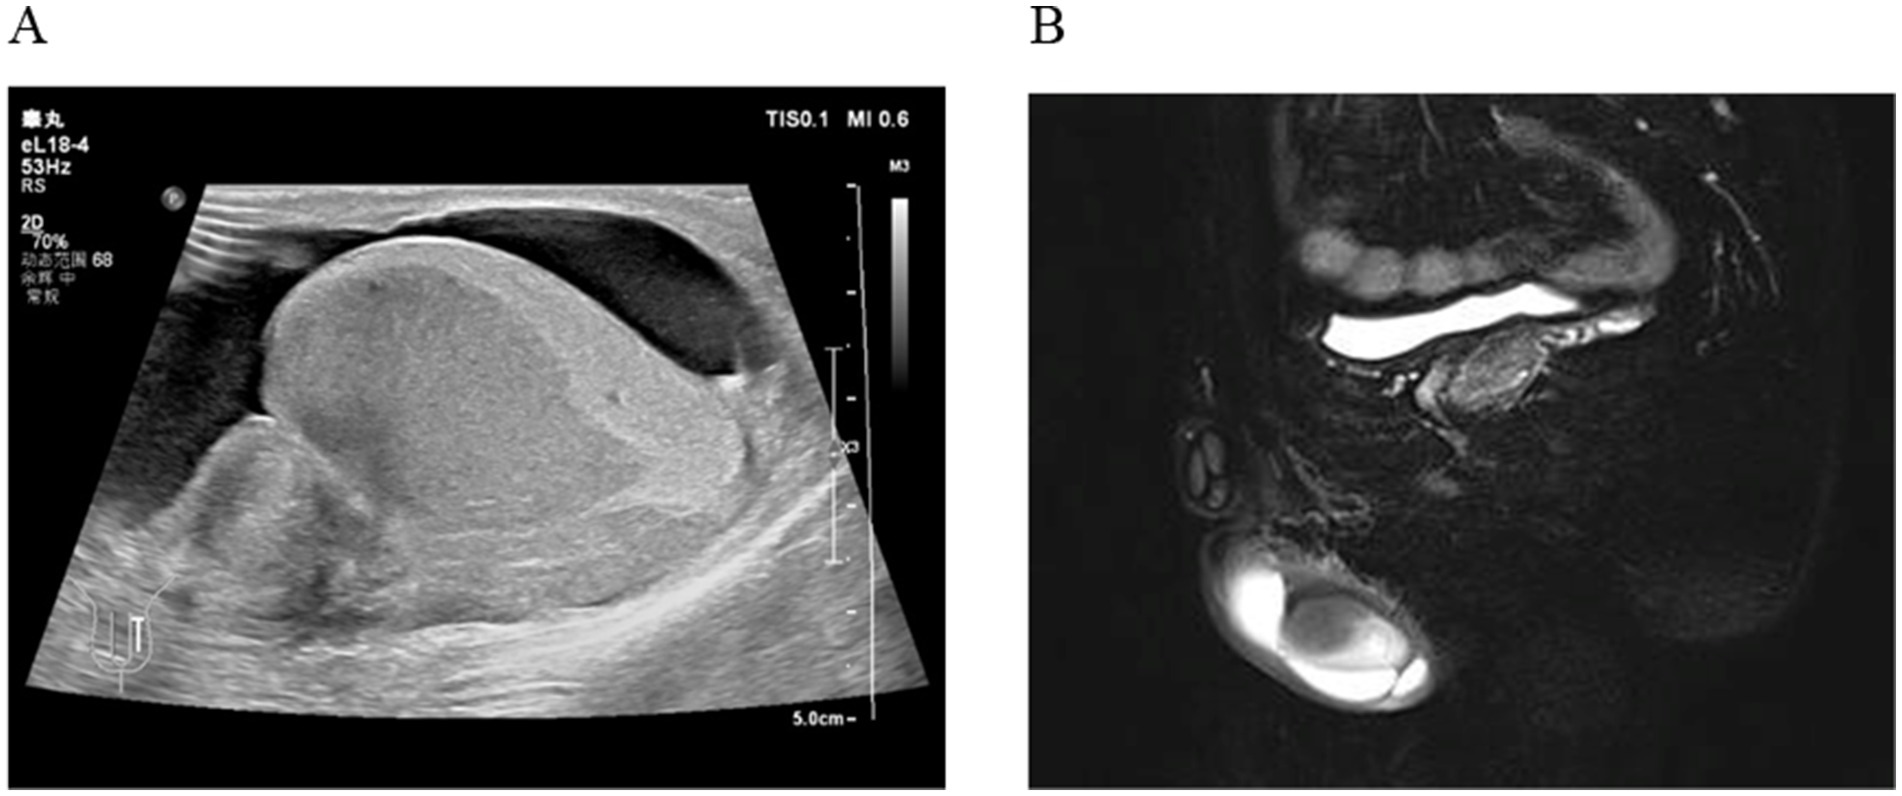

A 35-year-old man was admitted to Department of Urology on April 27, 2024, due to the discovery of a nodule behind the left testicle for 6 months, accompanied by pain for 2 days. Ultrasound shows a hypoechoic area in the left testicle, further examination is recommended. Enlarged left epididymis with abundant blood supply. There is a large amount of fluid accumulation in the left testicular sheath cavity (Figure 1A). Magnetic resonance imaging (MR) shows patchy abnormal signals in the left epididymis and testes, suggesting the possibility of infectious lesions; Bilateral testicular hydrocele (Figure 1B). He had a 10-year history of smoking (approximately 20 cigarettes per day) and no known family history of cancer, genetic diseases, or a history of long-term medication use. Additionally, there was no evidence of current or previous soft tissue tumors or history of radiation exposure.

Figure 1. (A) Ultrasound shows a hypoechoic area in the left testicle; Enlarged left epididymis with abundant blood supply. (B) MR shows patchy abnormal signals in the left epididymis and testes.